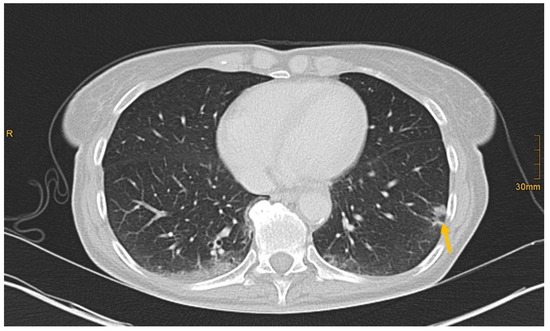

Figure 5. Subpleural bronchial carcinoma in the left lower lobe (arrow). Correctly identified by one radiologist without and by all three radiologists with given clinical information (Pain left hip with radiation into thoracic wall. Limited mobilization, reduced appetite. Obscure lesion of the lung on previous imaging.).

There are several reasons why tumors and metastases could be missed by radiologists. Firstly, the interpretation of oncological CT data sets is challenging; often multiple abnormalities are present in a single patient. Lesions may be benign and not always malignant. Therefore, findings could be undercalled and misinterpreted as benign (e.g., Figure 2) [1]. Findings may also be too small to be classified as malignant or may be overlooked (e.g., Figure 4). Additionally, findings, particularly of the lung, could be consistent with a postinflammatory benign aetiology due to configuration and subpleural location (e.g., Figure 5) [46]. Secondly, the so-called satisfaction of search represents another possible influence on the detection rate of malignant lesions. Satisfaction of search represents an interference of a radiological finding with the detection of further abnormalities [1,47]. Radiological image interpretation often follows a fixed procedure. Thus, as soon as a finding (mostly the primary tumor) is made, further lesions as metastases may be missed. This may explain the lower rate of true positive metastatic findings. Further reasons for missed metastatic lesions can be assumed. Metastases are often small, not reliably distinguishable from benign lesions and therefore an unequivocal diagnosis is often impossible without follow-up imaging or complementary procedures such as MRI, hybrid imaging, or biopsy. Moreover, imaging criteria for lymphogenous metastases are often controversial, an accurate identification is challenging. In the past, a short axis diameter of 1 cm was used as the cut-off value for enlarged, malignancy-susceptible lymph nodes [1]. Recent studies suggest different parameters for various anatomic regions, such as 6 mm for retrocrural or 8–10 mm for pelvic lymph nodes. However, enlarged lymph nodes are not always malignant. They also could have an inflammatory aetiology or normal-sized lymph nodes may have tumor involvement [48]. Of course, there are numerous cases in the present study that had been solved correctly. Figure 3 shows an example of a pancreatic carcinoma correctly diagnosed by all three radiologists irrespective of clinical information.